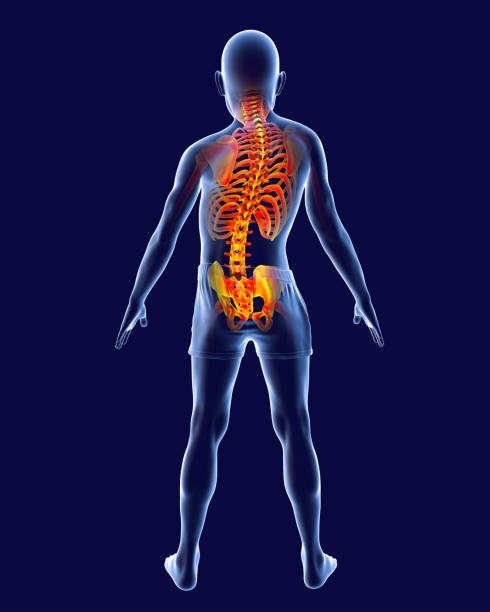

척추 측만증은 척추의 곡선이 비정상적으로 증가하여 등이 한쪽으로 치우치는 질환 입니다.

이로 인해 등이 비대칭적으로 변형되며 체형이 휘어지게 되는데요.

척추 측만증은 통증과 불편감을 유발할 뿐만 아니라 심각한 경우에는 신경 손상과 호흡 기능 저하를 초래할 수 있습니다.